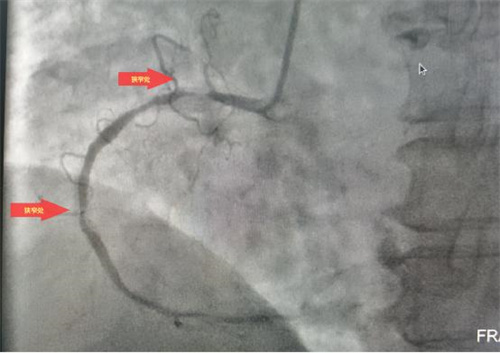

據(jù)了解,此次順利完成經(jīng)皮冠狀動脈內(nèi)支架植入術的患者共有4位,其中一名68歲老年女性患者,因胸悶氣促6余年,活動后明顯加重入院治療。經(jīng)冠脈造影檢查,發(fā)現(xiàn)左前降支次全閉塞、右冠99%重度狹窄,三支血管重度病變,情況危急。經(jīng)病情評估后,與患者家屬溝通,決定立即對右冠實施冠狀動脈球囊擴張加支架植入術。在上級專家的指導下,心病科團隊成功擴張了狹窄血管、植入支架,手術順利,患者術后安返病房,為患者后續(xù)治療創(chuàng)造了有力條件。